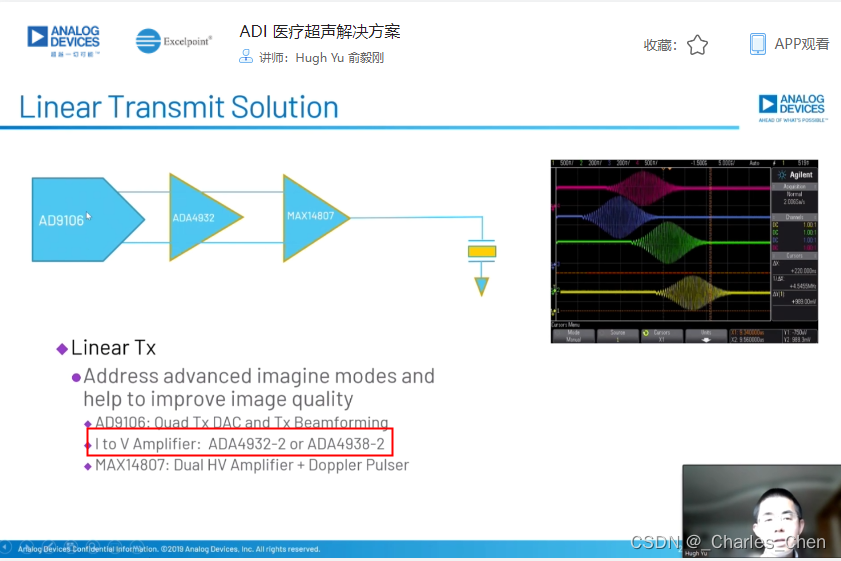

数字发射波束成形器用于产生所要求的数字发射信号,以正确的时间和相位生成聚焦发射信号。高性能超声系统可通过任意波形发生器产生复杂的发射波形,从而优化图像质量。这些情况下,发射波束成形器以大约40MHz速率生成8位至10位数字字符,并以此产生所要求的发射波形。数/模转换器(DAC)将数字波形转换成模拟信号,通过线性高压放大器进行放大,用于驱动传感器单元。由于这种发射技术占用较大体积,而且价格昂贵、需要消耗较高能量,所以,这种架构只限于昂贵的非便携设备。多数超声系统并不使用这种发射波束成形技术,而是采用多级高压脉冲发生器产生需要发射的信号。在这种替代方案中,利用高集成度、高压脉冲发生器快速切换传感器单元至适当的可编程高压电源,产生发射波形。为了产生一个简单的两极发射波形,脉冲发生器需要交替地将传感器单元切换到由数字波束成形器控制的正、负发射电压。更复杂的设计可以让传感器单元切换至多路电源和地,从而产生更复杂、性能更好的多重波形。